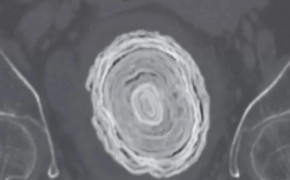

Các bác sĩ phát hiện một viên sỏi bàng quang khổng lồ, to bằng quả bóng chày, khi siêu âm cho một phụ nữ 72 tuổi có triệu chứng đau đớn và tiểu ra máu.